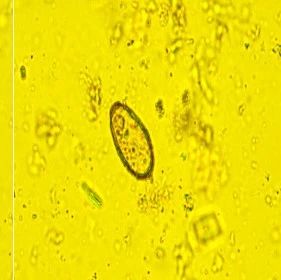

• 到底是阳性还是阴性?——尿检避坑指南请查收

• 检验科破解“血尿”谜案:72岁患者的生死惊魂